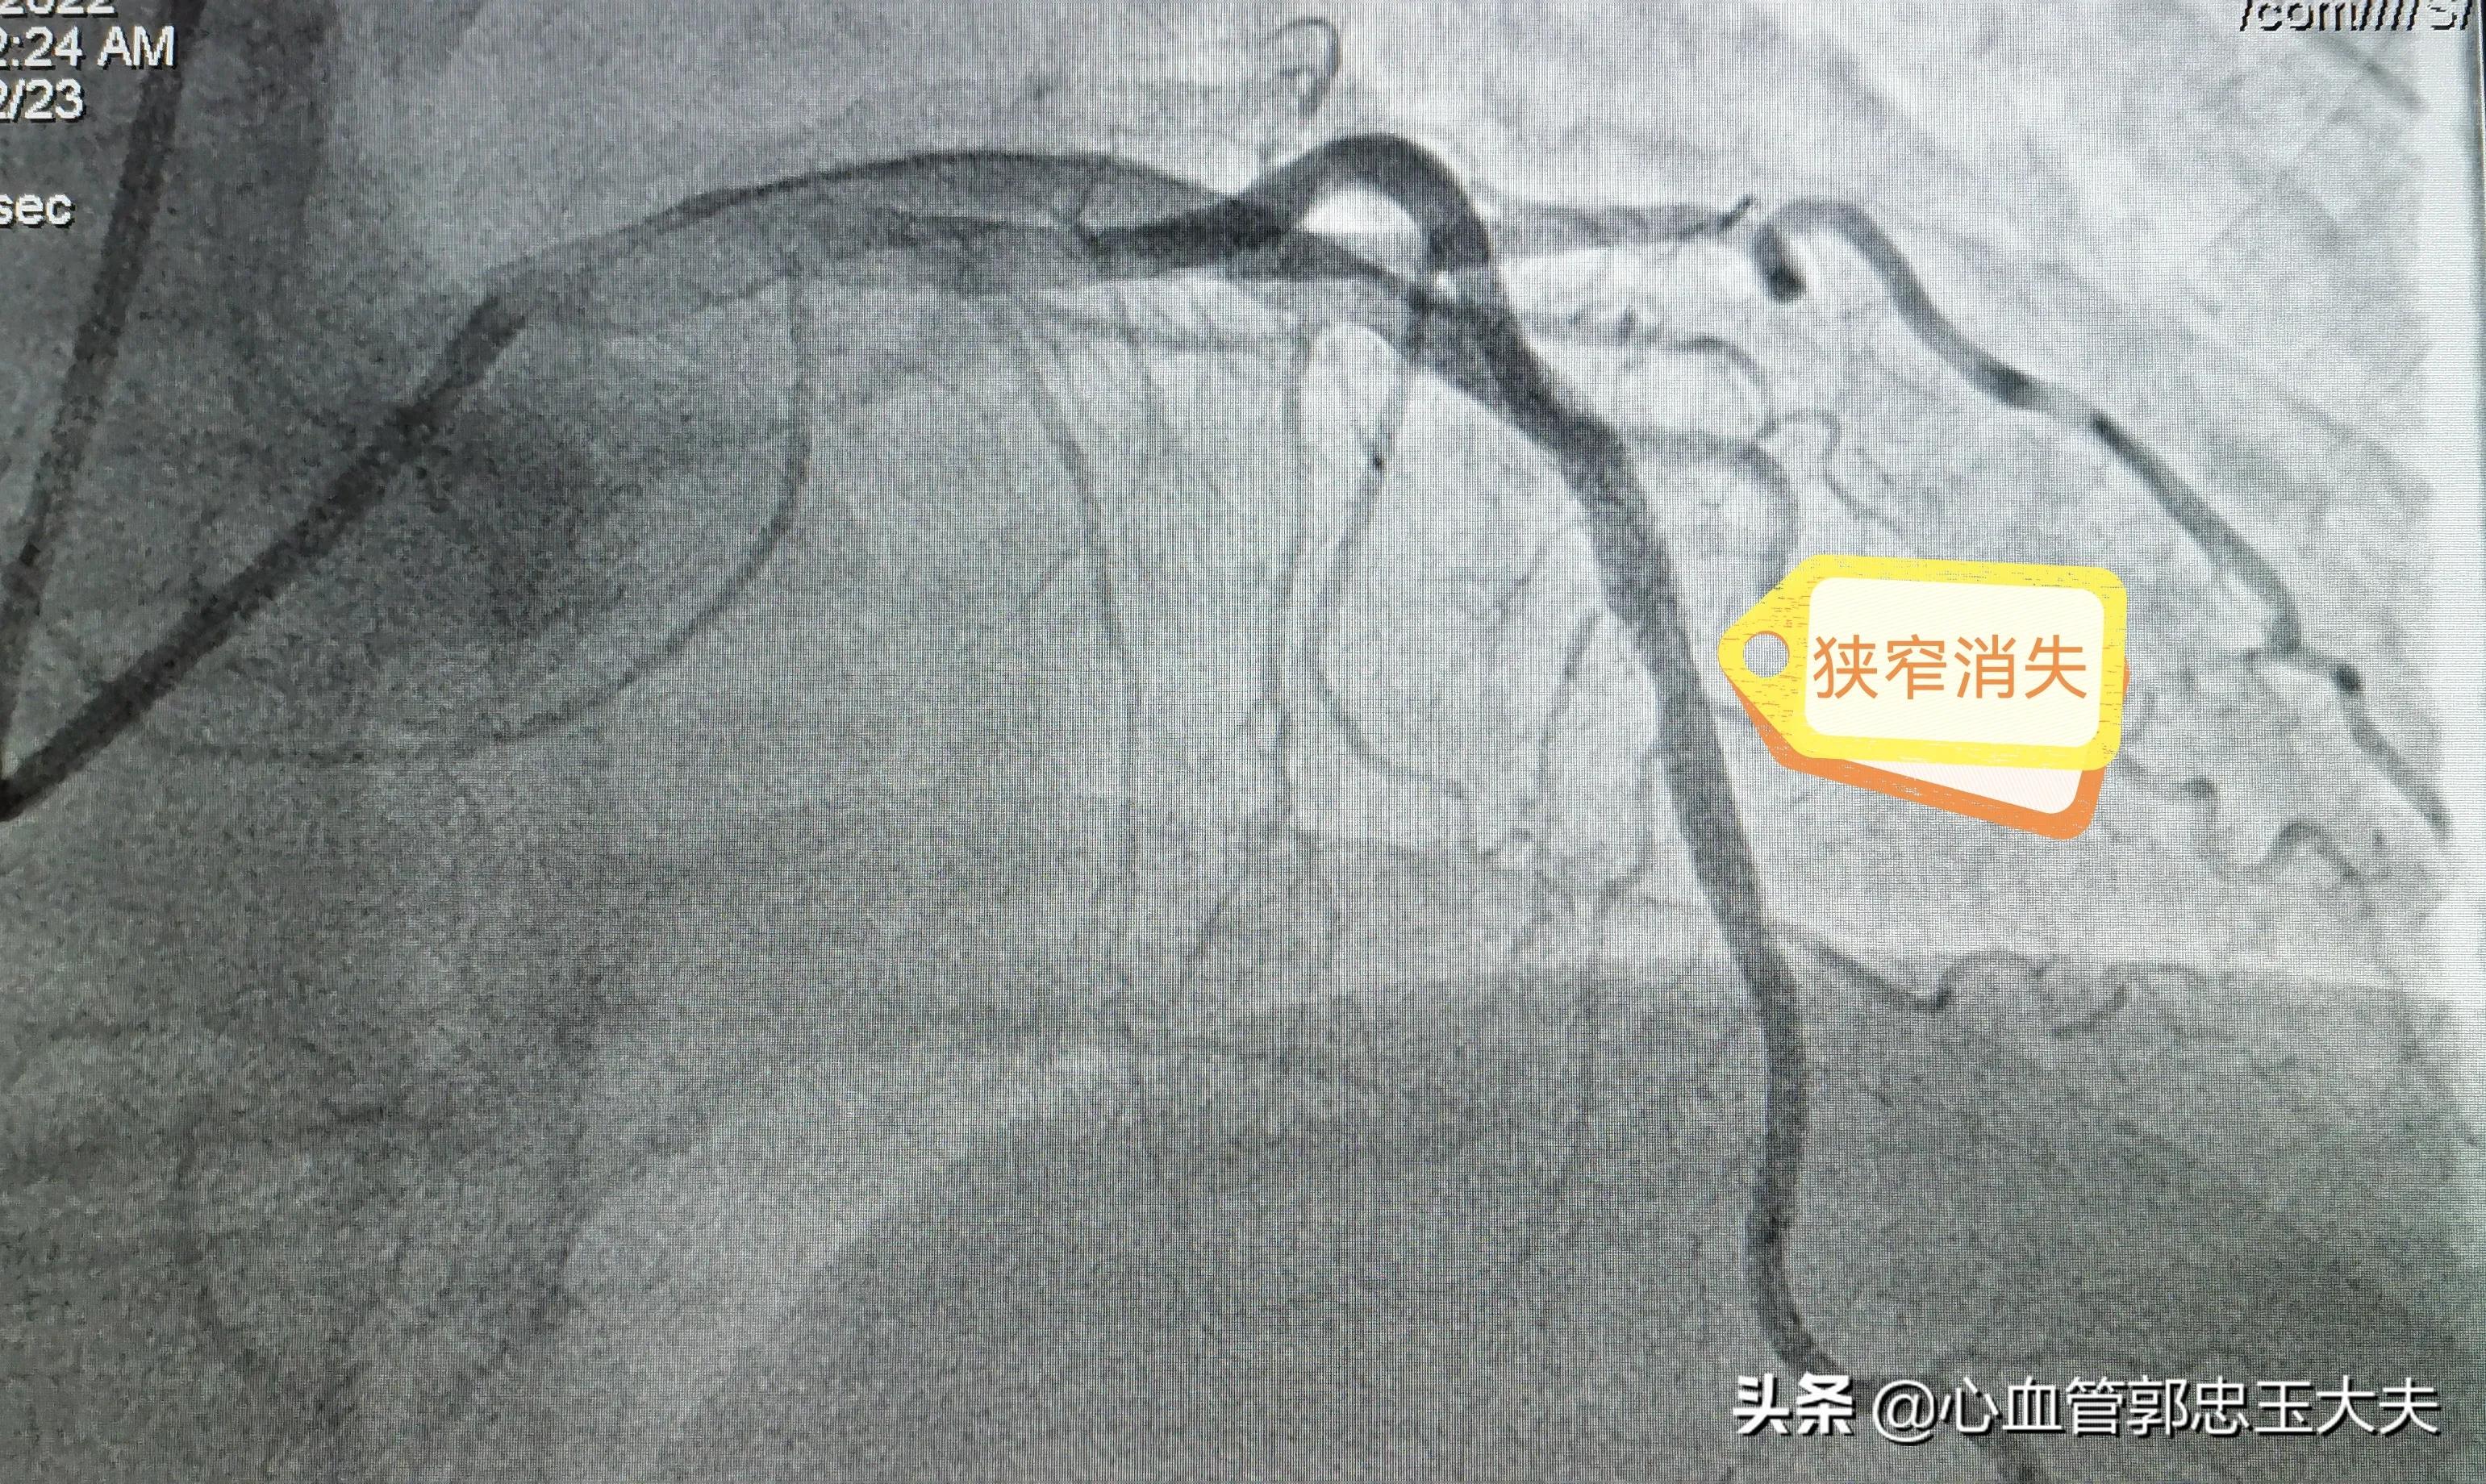

由于患者已经做过一次支架,去年5月份复查过一次造影血管是“好的”,对再次造影很*制抵**,考虑到 典型的劳力性心绞痛症状及心电图缺血改变 ,还是 决定冠脉造影检查 。经过与本人及家属反复沟通,终于同意造影。术中造影示:前降支近段到中远段可见支架影,支架内血流顺畅, 支架内远端及边缘血管80%狭窄 ,按照 支架内再狭窄定义:支架内及边缘5mm内血管再次50%以上狭窄 。考虑 支架内再狭窄 。患者及家属拒绝再次植入支架,故选用药物球囊扩张,术后狭窄消失,未见夹层形成。手术圆满结束。

狭窄消失